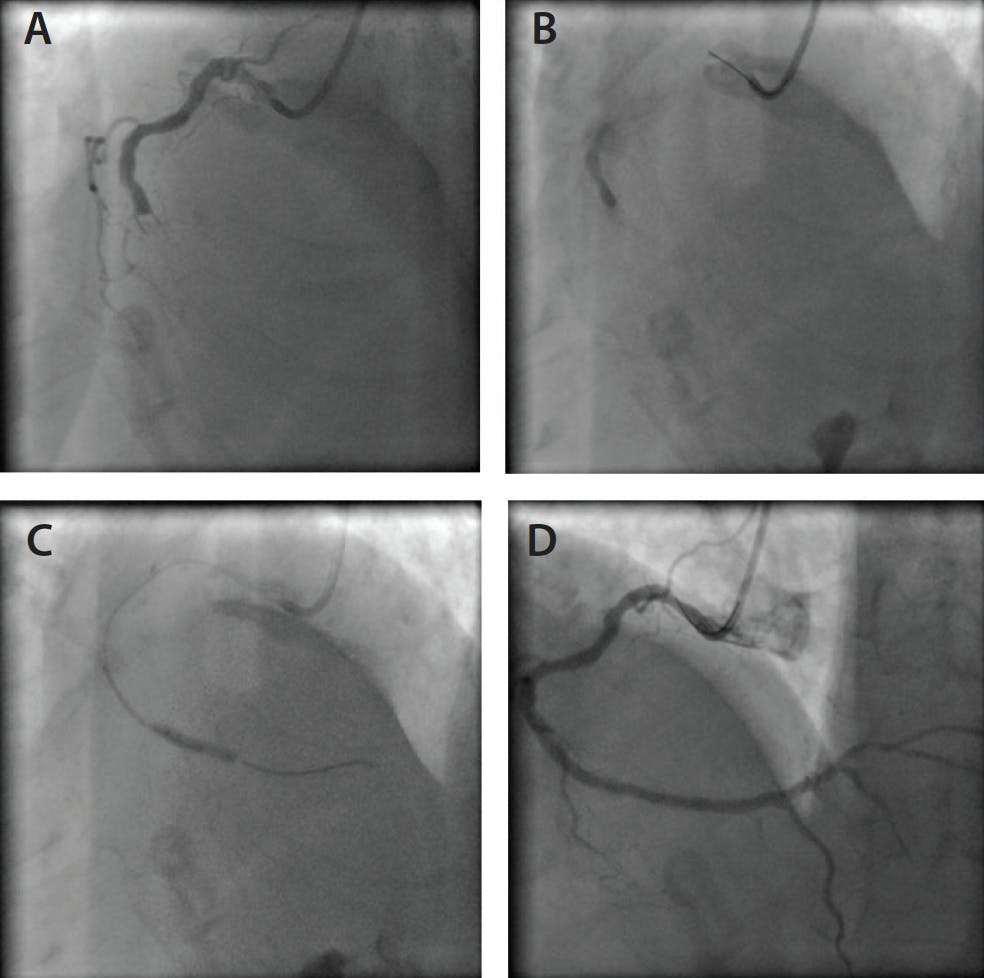

AFR was recently described as a technique for the antegrade treatment of CTOs.4 It consists of creating multiple fenestrations of the dissection flap, separating the false and true lumen to permit CTO recanalization. A guidewire is advanced in an antegrade fashion in the subadventitial space beyond the distal cap of the occlusion. A second low–tip load polymer-jacketed guidewire is then brought into close proximity with the first one, with its tip just proximal to the distal cap. A balloon sized 1:1 with the artery is subsequently advanced onto the first guidewire and inflated at nominal pressure at the level of the distal cap, creating transient fenestrations between the false and true lumen that can be effectively engaged with the second guidewire, thus achieving re-entry. This maneuver can be successfully applied to treat IOCD during standard PCI (Figure 2).9

Figure 2. AFR technique: thrombotic occlusion of the middle right coronary artery (A); no reflow due to coronary wire dissection (B); progression of the polymer-jacketed wire in the true lumen across the fenestrations created by 3.5-mm balloon inflation-deflation (C); and final result after multiple DES implantations (D).